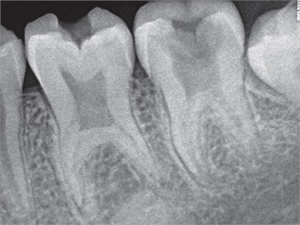

X-ray of taurodontic teeth

The diagnosis of a taurodont is confirmed by a radiograph in which an enlarged pulp chamber, lower pulpal floor and lack of constriction at the junction of cementum and enamel are seen.